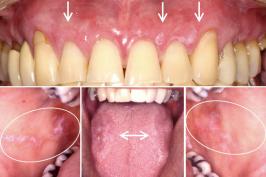

Onde ocorre mais o câncer dentro da boca

14.02.2026 06h32

COLUNISTA

Câncer bucal: só apelando para o Abujamra

31.05.2025 06h26

Confira as causas do câncer bucal

25.05.2024 05h51